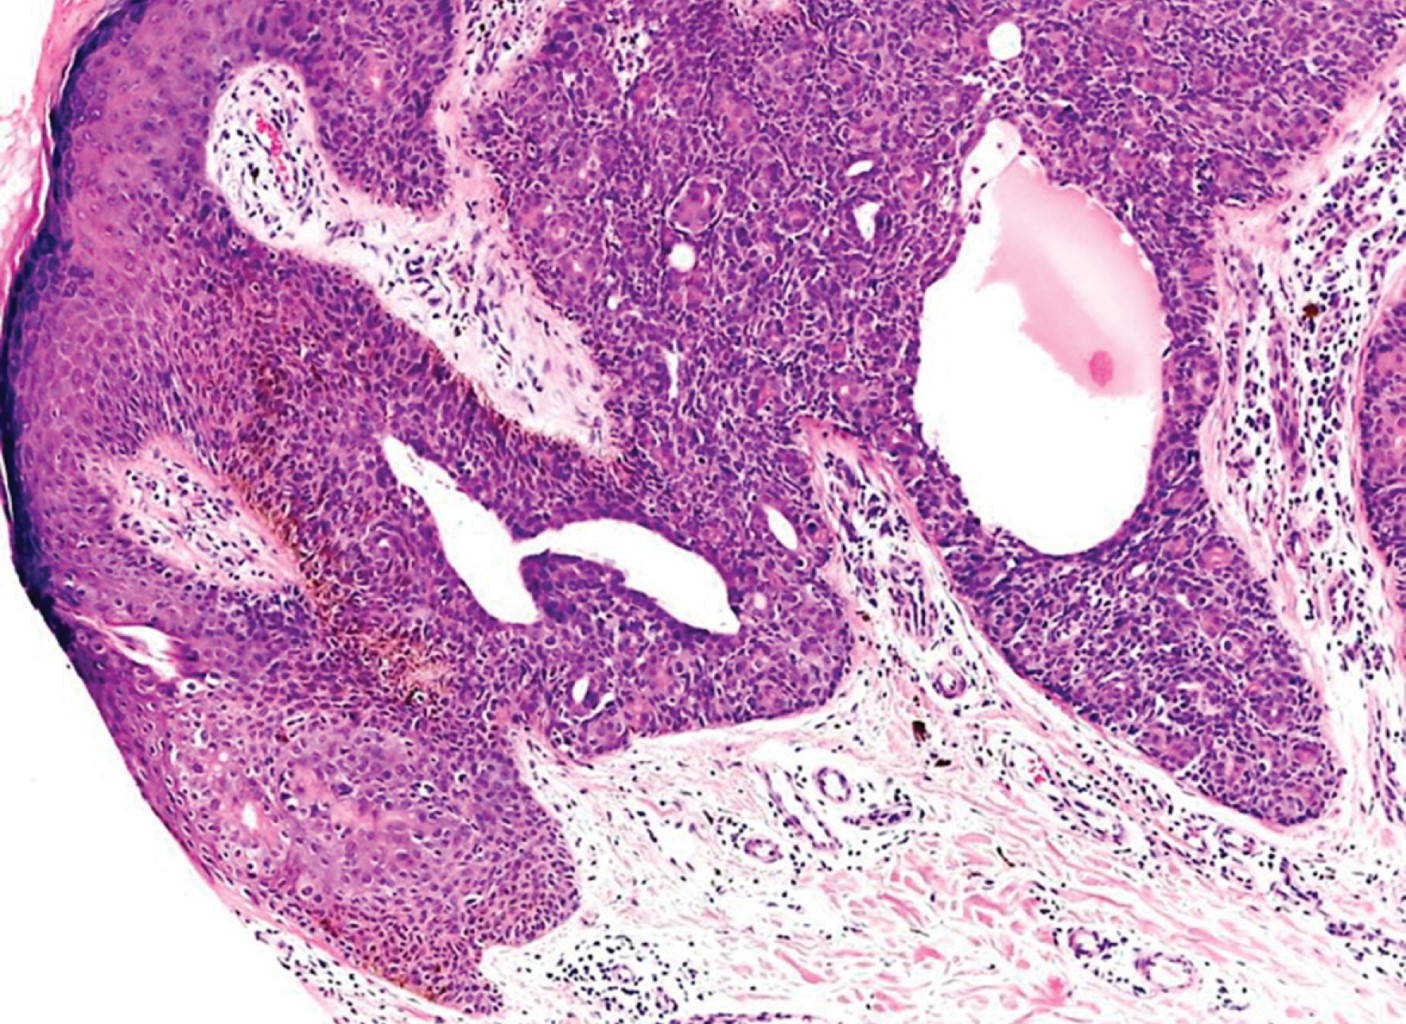

Con la sospecha clínica de probable poroma ecrino se realiza biopsia excisional. El estudio histopatológico reporta neoformación Exofítica, cuya epidermis muestra hiperqueratosis paraqueratósica (Figura 3). En todo el espesor de la dermis se observan cordones tumorales conectados con la epidermis, los cuales se anastomosan atrapando papilas (Figura 4); están constituidos por células de núcleos basofílicos, algunas de las cuales presentan núcleos grandes e hipercromáticos, mitosis anormales y metaplasia escamosa; presentan estructuras ductales y pigmento melánico, rodeados por una moderada reacción inflamatoria (Figuras 5 y 6). El diagnóstico histopatológico fue de porocarcinoma ecrino. En el Servicio de Dermatooncología de esta Unidad se efectúa extirpación quirúrgica más amplia, con margen de 7 cm, con reparación del defecto llevando a cabo un injerto, sin evidenciar lesión tumoral remanente en la histopatología. Al considerarse un tumor con alto potencial metastásico, se envía al paciente a hospital de tercer nivel para hacer estudios de extensión y seguimiento.

Figura 3

Figura 4